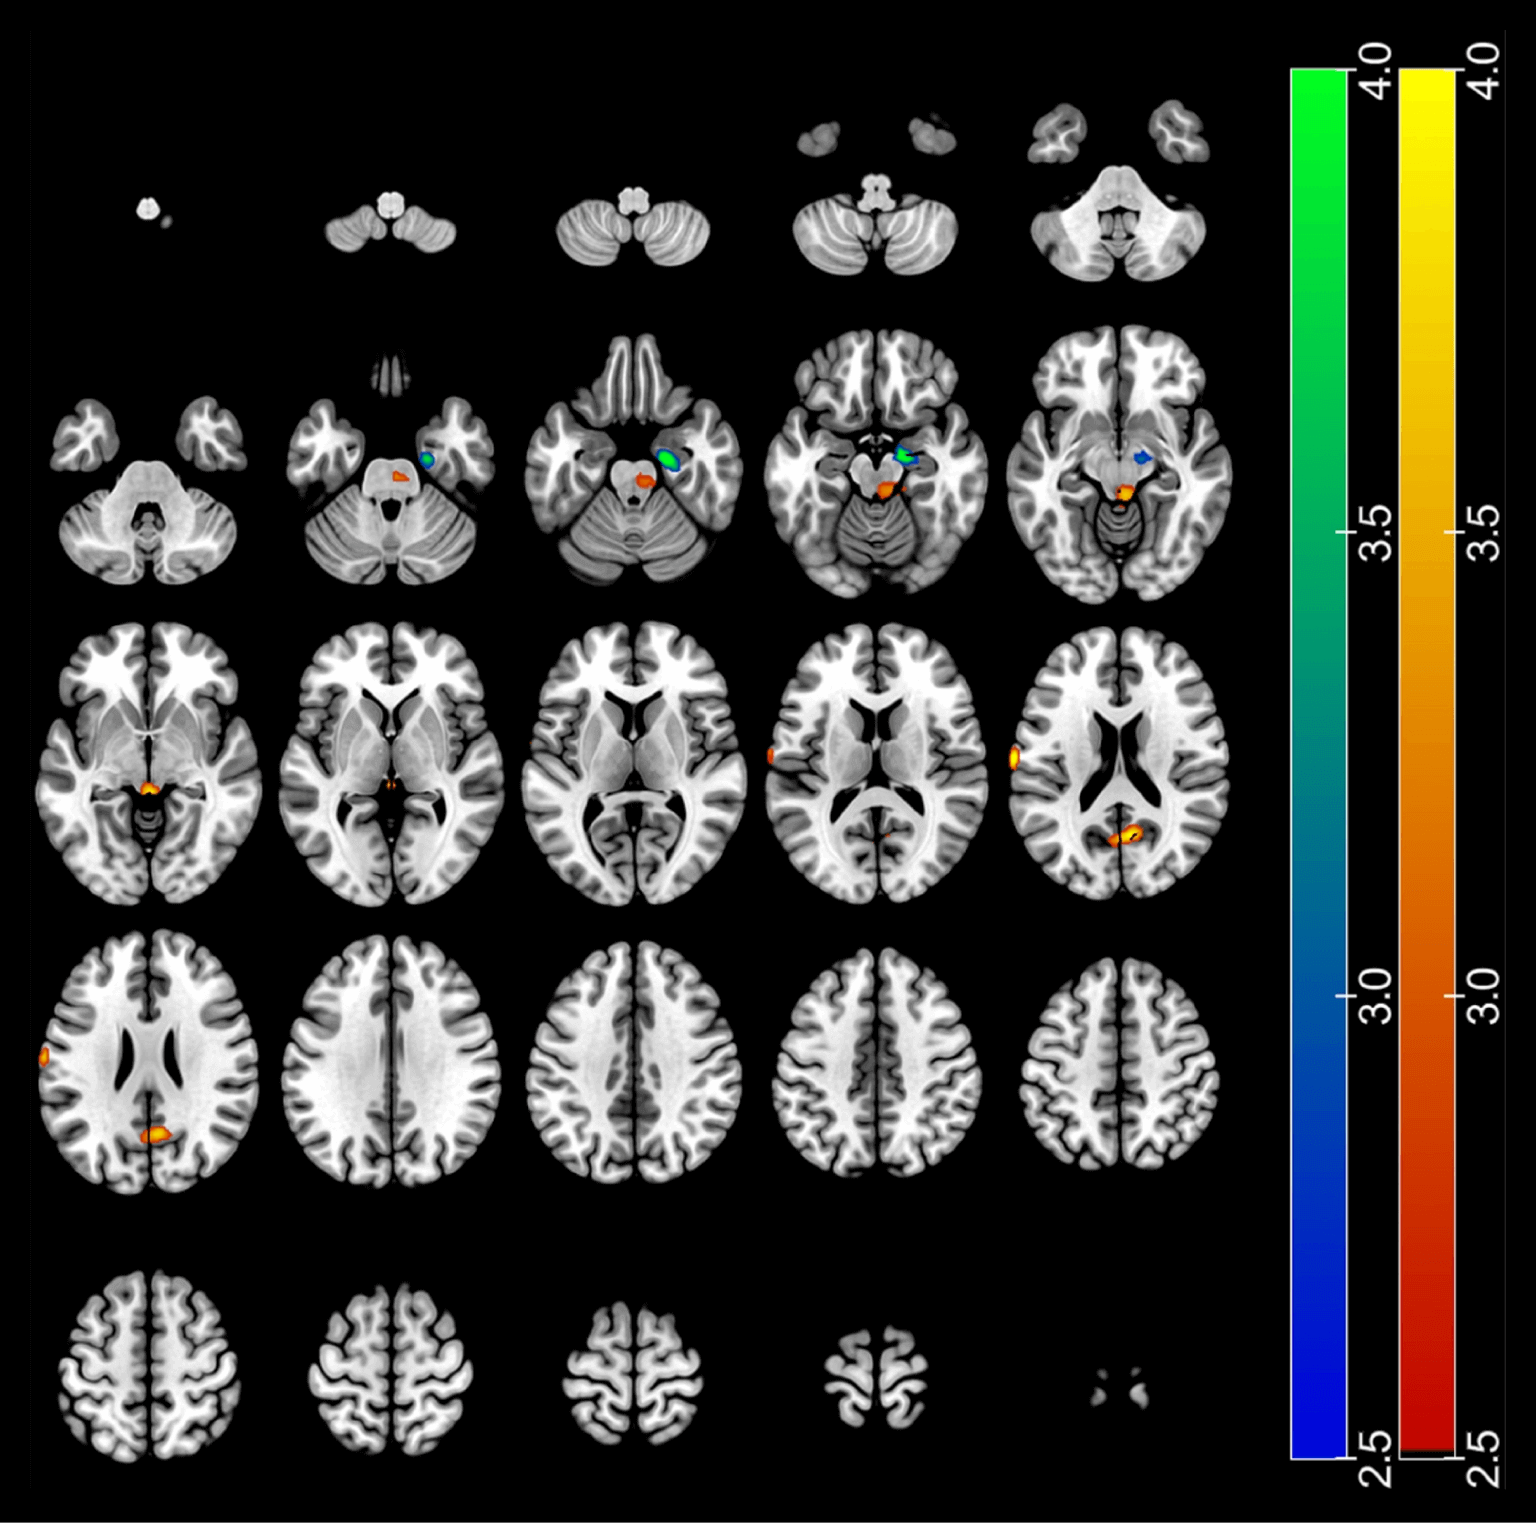

PDE5 inhibition has been shown to increase cognitive function by promoting better blood flow to the brain and instigating emotional arousal. Brain scans have found that daily use of tadalafil in subjects with cognitive impairment results in increased blood flow to regions of the brain associated with cognitive function: the gyrus, precuneus, and brainstem. By impacting this part of the brain, PDE5 inhibition enhances attention, memory, abstraction, orientation, language, and naming.

Changes in Regional Cerebral Blood Flow at 8 weeks with Daily Tadalafil The red-yellow color indicates the increase in the follow-up versus at baseline, while the blue-green color indicates a decrease in the follow-up versus at baseline

Fig.1 - Choi JB, Cho KJ, Kim JC, Kim CH, Chung YA, Jeong HS, Shim YS, Koh JS. The Effect of Daily Low Dose Tadalafil on Cerebral Perfusion and Cognition in Patients with Erectile Dysfunction and Mild Cognitive Impairment. Clin Psychopharmacol Neurosci. 2019 Aug 31;17(3):432-437.